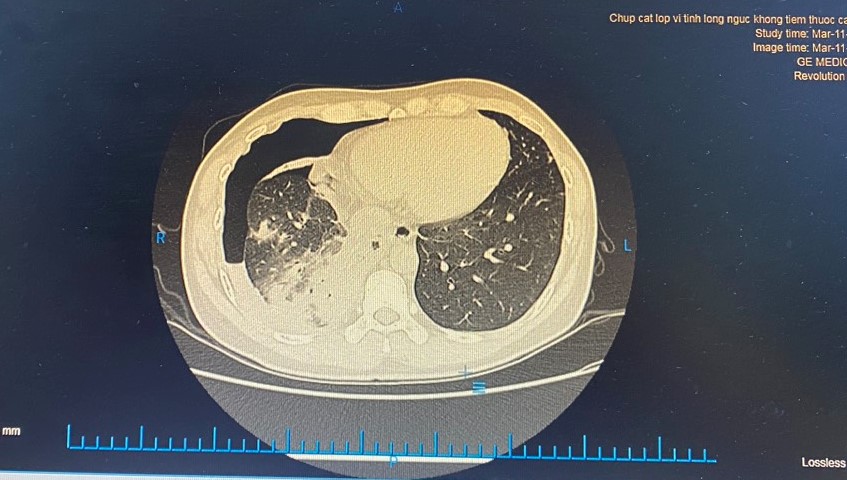

Bệnh nhân nam, 37 tuổi vào Bệnh viện đa khoa quốc tế Hải Phòng vì đau ngực, hạ sườn phải; trước vào viện 3 ngày, mệt tăng dần, ho húng hắng. Bệnh nhân có tiền sử hay ăn gỏi cua, cá, tôm. Gia đình nuôi nhiều chó, mèo. Qua thăm khám và các chỉ định cận lâm sàng cần thiết: Chụp CT ngực phát hiện hình ảnh viêm phổi, tràn dịch – tràn khí màng phổi; CT bụng hình ảnh áp xe gan trái. Bác sĩ tiến hành siêu âm lấy dịch màng phổi, hút ra dịch mủ loãng. Đồng thời kết quả xét nghiệm phát hiện người bệnh có sán lá phổi, giun đũa chó mèo.

- hình ảnh viêm phổi, tràn dịch – tràn khí màng phổi